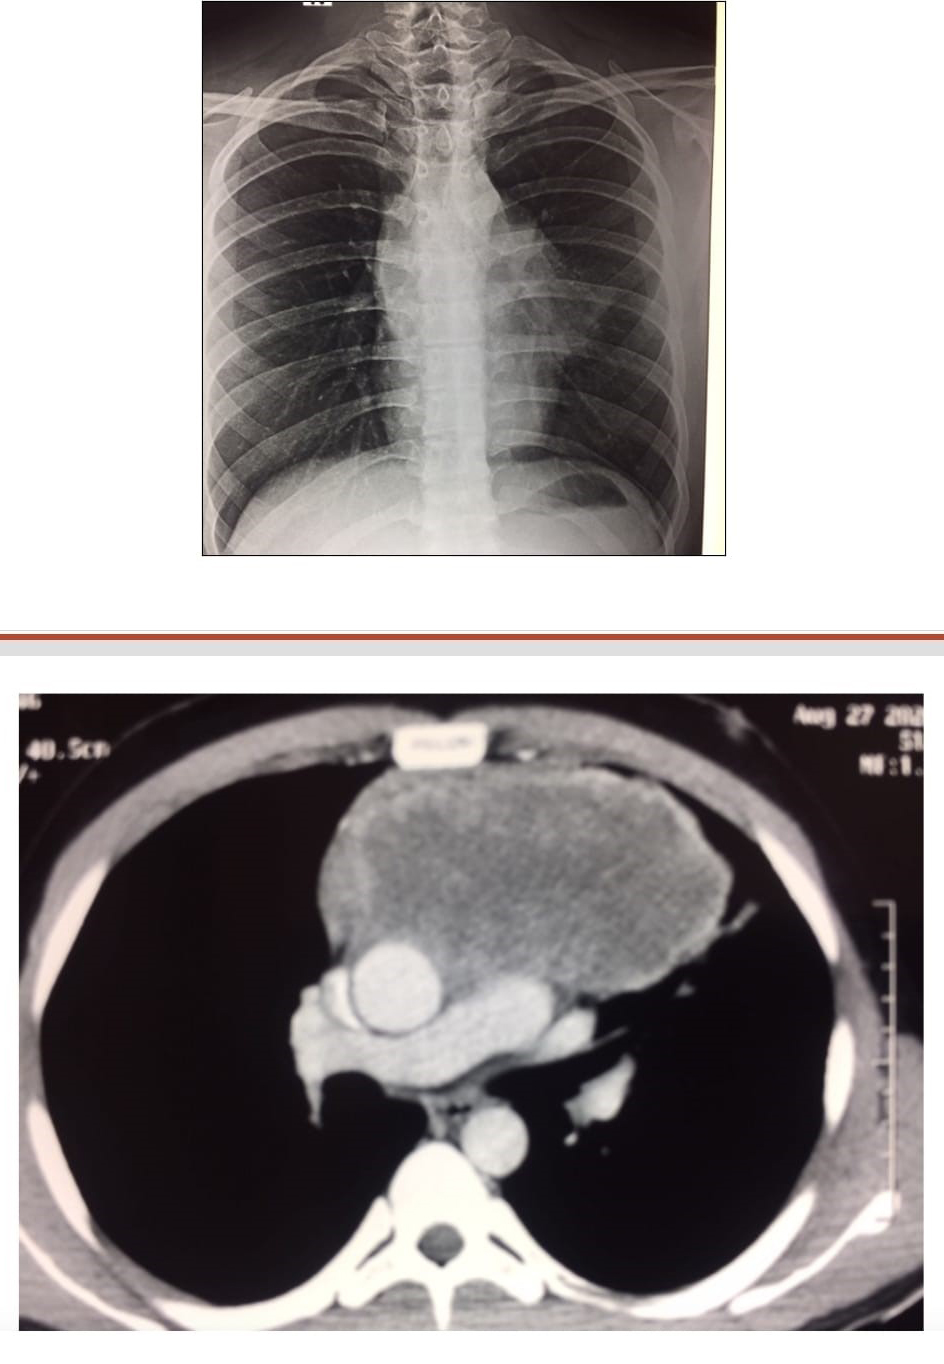

22 years old female medical student with recurrent cough since childhood:

Question Image